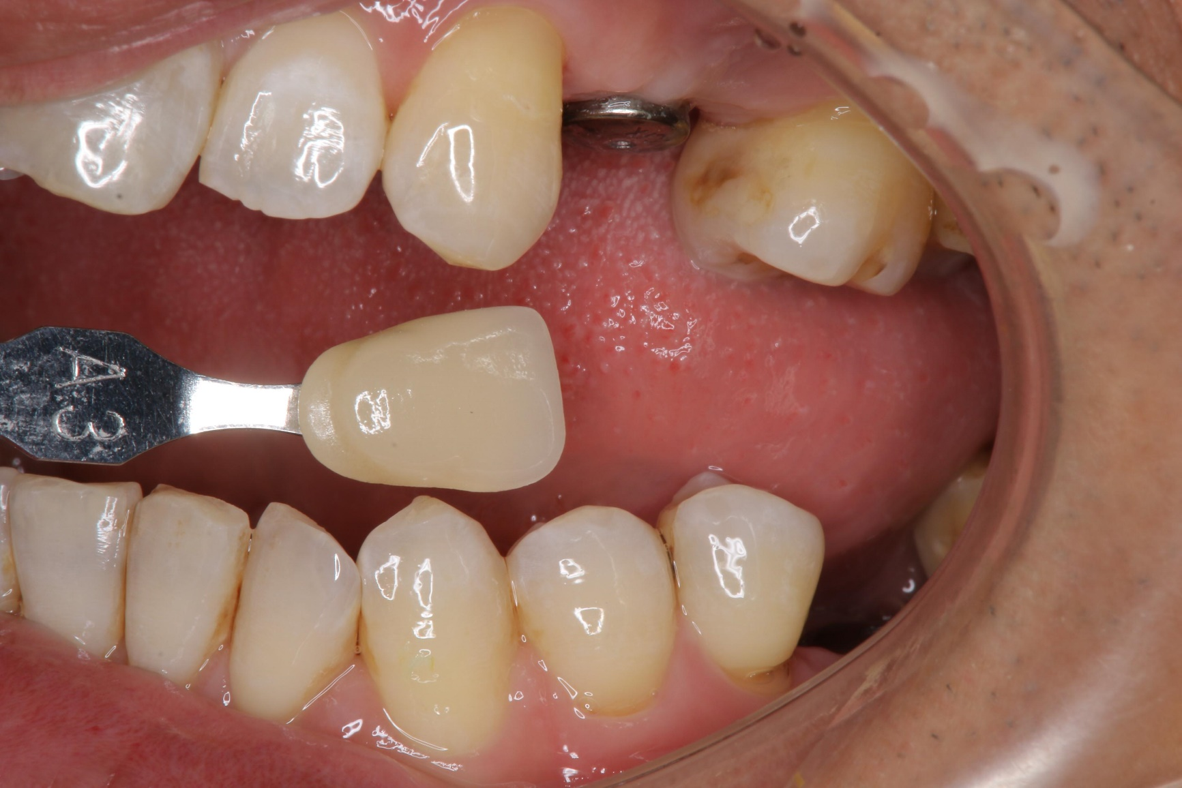

臨床照相比色